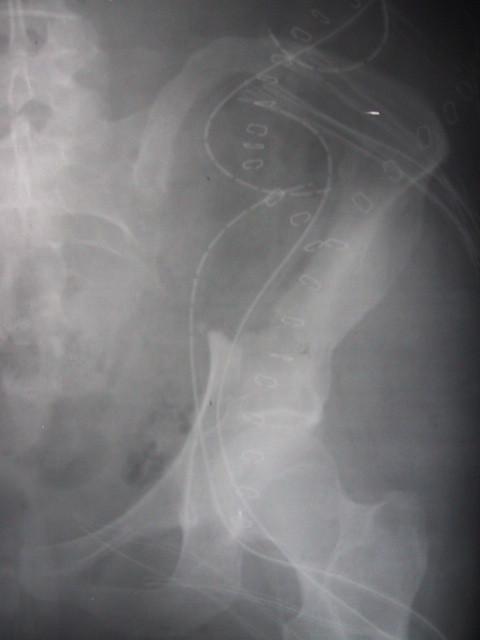

A 34-year-old female presented with BFH at a rare anatomical location on both sides of the os ilium which was larger than earlier reported BFH of the bone. Surgical resection was performed successfully including resection of the inner pelvic ring and reconstruction of the linea terminalis using a non-vascularized fibular autograft. At 18 months after tumor resection and reconstruction of the pelvic ring, with interposition of a free vascularized fibula graft patient has an excellent clinical oncological and functional outcome.

一名34岁女性在双侧髂骨罕见的解剖位置出现BFH,其尺寸大于先前报道的骨源性BFH。成功实施了手术切除,包括切除骨盆内环并使用非血管化腓骨自体移植重建耻骨梳韧带。在肿瘤切除及骨盆环重建18个月后,通过置入游离血管化腓骨移植,患者获得了出色的临床肿瘤学及功能预后。